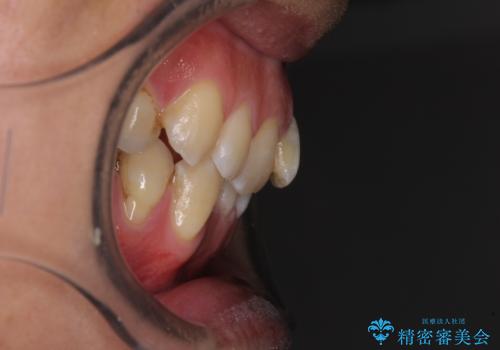

- 前歯のデコボコを気にして来院された患者様です。

下顎前歯のデコボコが特に強く、治療を早く終えることを考えるとワイヤー装置がお勧めですが、ワイヤー装置の異物感は避けたいのでインビザラインを希望されていました。

下顎にワイヤー装置を装着し、暫くしたところでやはりインビザラインにて矯正治療をしたいとのことで、インビザラインに切り替えました。

短い期間でしたがワイヤー装置を使用したことでデコボコが解消されたため、インビザラインの比較的短い期間で矯正治療を行うことができました。